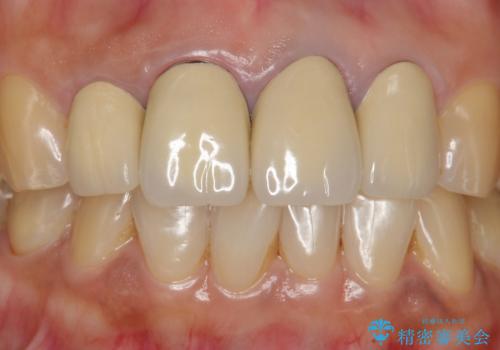

- 前歯のセラミック治療から5年経過した患者様です。

数年ぶりにメンテナンスに来て下さいました。

治療した上の前歯4本は全く問題がないそうで、「どうしてこんなに長持ちするんですか?」と聞かれた程です。

5年前のクラウン装着時と比較したところ、歯肉が成熟し歯間乳頭ができており、より天然歯のように自然に見えました。

患者様の良好なセルフケアと精密な適合の良いクラウンにより、歯肉の腫脹や退縮も認められませんでした。